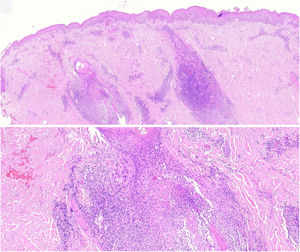

The histopathological slides that gave rise to diagnosis of FMF were evaluated by 2 dermatopathologists (SM and XR), blinded to clinical and follow-up data. The histological parameters assessed were based on the studies by Santen et al.12,16,17 and are as follows: histological subtype (1. early-stage or patch disease; 2. early-stage plaque; 3. advanced plaque; 4. tumor); extension of neoplastic infiltrate (1. scarce; 2. prominently perifollicular and perivascular confined to the perifollicular area; 3. confluent perifollicular and interfollicular; 4. complete diffuse); percentage of atypical cells in infiltrate (<10%; 11–25%; >25%); degree of folliculotropism (mild, moderate, and extensive); epidermotropism (absent or present); syringotropism (absent or present); follicular mucinosis (absent or present); eosinophilic infiltrate (absent or present); Ki-67 expression (less than 10% or greater than 10%); and presence of other microscopic findings such as transformation to large cells or CD8 phenotype. The plaques were assessed with hematoxylin–eosin and with immunohistochemical markers (examples of an early-stage plaque and an advanced one are shown in Fig. 1 and Fig. 2, respectively).

Early-stage plaque. Scarce perifollicular atypical lymphoid infiltrate can be observed, with prominent follicular mucinosis, epidermotropism with linear bands of lymphocytes at the dermal–epidermal junction. Of note is the fibrotic background and poikiloderma, as well as some apoptotic keratinocytes and melanophages.